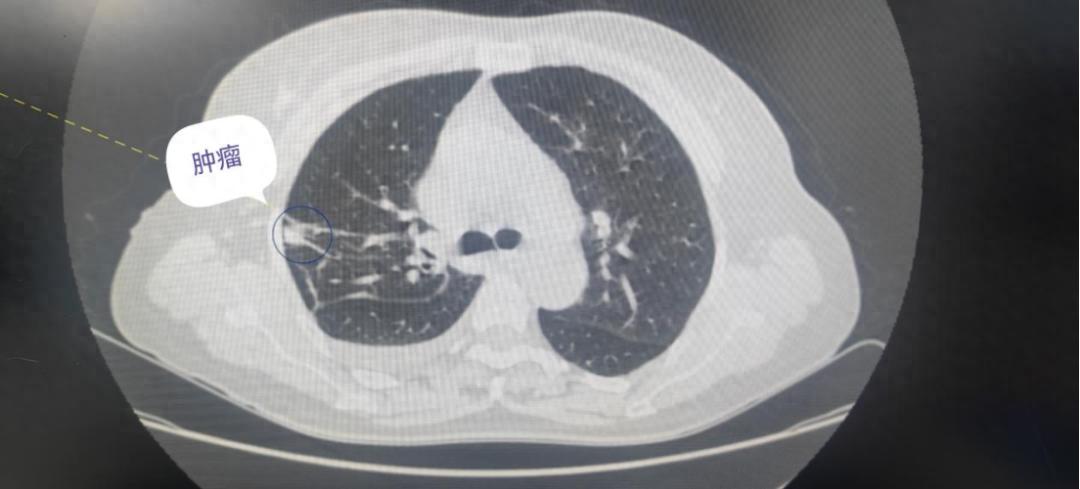

在与疾病抗争的战场上,每一次技术的突破都为患者点亮希望之光。近日,遂宁市安居区人民医院成功完成首例胸腔镜下肺肿瘤手术,这不仅是一个患者康复的好消息,更标志着医院胸外科迈向了全新的发展阶段,为众多肺部疾病患者带来了更先进、更精准的治疗选择。日前,黎女士因左肩疼痛不适,在医院门诊进行 CT 检查时,意外发现双肺散在实性、亚实性结节,其中最大的结节位于右肺上叶,约 1.4cm×1.3cm,胸部增强 CT结果显示右肺上叶尖段部分实性结节,LU-RADS 分级为 4A 类,需进行穿刺活检。出于对安居区人民医院的信任,黎女士入住呼吸与危重症医学科进行下一步治疗。

在 CT 引导下,医生为她成功实施了经皮右肺结节穿刺活检术,病理检查结果显示为原位癌。医院相关科室会诊后,认为患者具备外科手术指征,建议进行手术治疗。遂转入胸外科,科室医护团队迅速行动,为她完善各项术前准备工作。